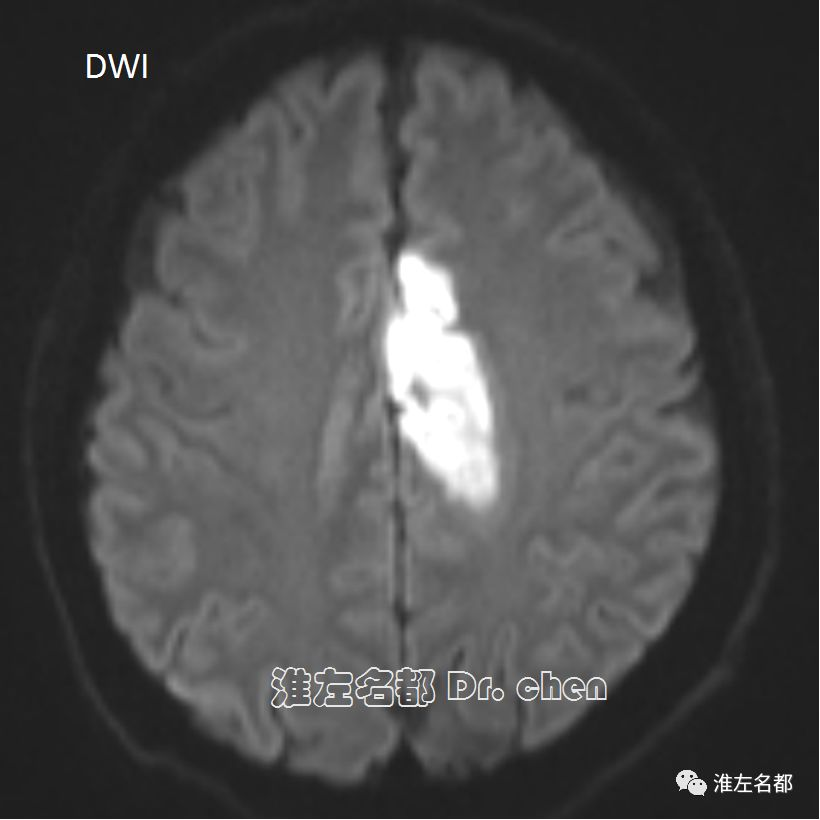

△DWI:左侧额叶内侧急性梗死